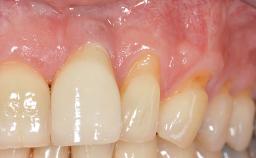

Soft-Tissue Volume Augmentation Using a Connective-Tissue Graft Harvested from the Maxillary Tuberosity

In 1983, a 51-year-old non-smoking patient was referred for the treatment of moderate chronic periodontitis. At the initial examination, 47% of sites exhibited probing depths of 4 to 6 mm. Periodontal therapy consisted of initial periodontal treatment including oral-hygiene instructions and supra- and subgingival debridement, followed by periodontal surgery to eliminate residual pockets.

Soft Tissue Anatomy Intact Defective